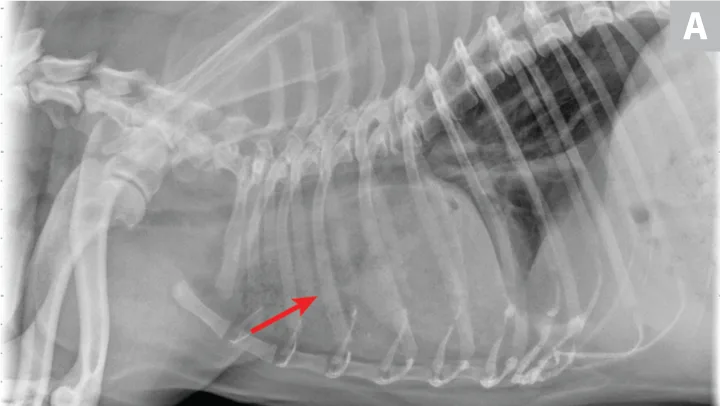

Nonspecific illness and respiratory signs may be appreciated. Leukocytosis, left shift, and pyrexia may be present.34 Radiographs often reveal an alveolar pattern, trapped gas (vesiculated), and/or pleural effusion. Bronchial malpositioning is uncommon (Figure 6).35 Confirmation via ultrasonography, bronchoscopy, and/or CT is recommended.36,37 Pleural fluid varies widely in gross and cytologic appearance. Although nonspecific, the presence of pleural fluid, alveolar disease, and acute respiratory signs is suggestive. Immediate lung lobectomy is warranted.

FIGURE 6

Lung lobe torsion. Note classic vesicular pattern associated with gas trapping and pleural effusion. Bronchial attenuation or displacement is subtle and often absent.